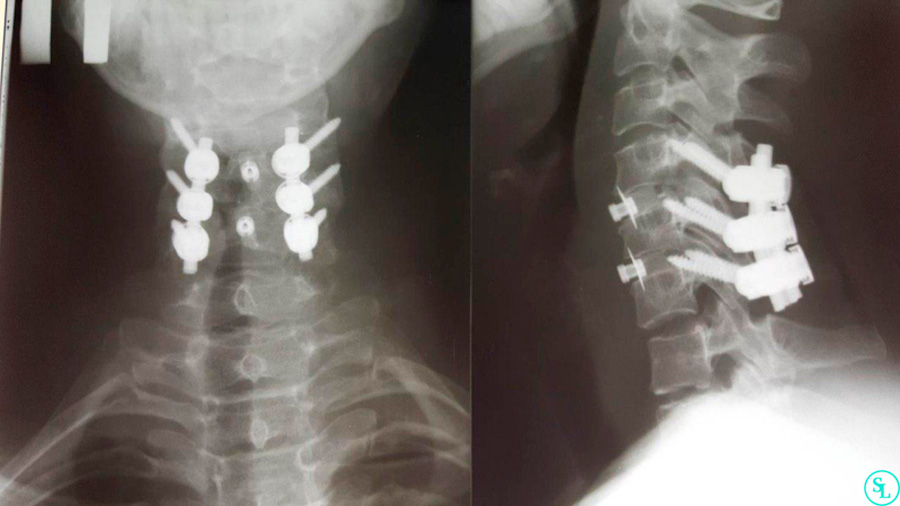

Проведена микрохирургическая операция – корпорэктомия шейного отдела позвоночника с имплантация кейджа и установкой вентральной пластины в сегменте от 3-го до 6-го шейного позвонка.

На послеоперационных снимках КТ шейного отдела позвоночника никаких признаков гигромы или кровотечения не обнаружено. На десятый день после операции пациентка выписана под наблюдение врачей по месту жительства.